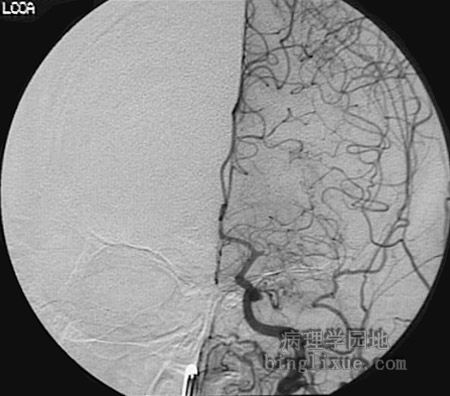

左颈总动脉主要分支栓塞(血管造影)

血管造影显示左颈总动脉的主要分支的栓子阻塞。

This angiogram demonstrates an embolic obstruction of a branch of the left common carotid artery just past the first main bifurcation.